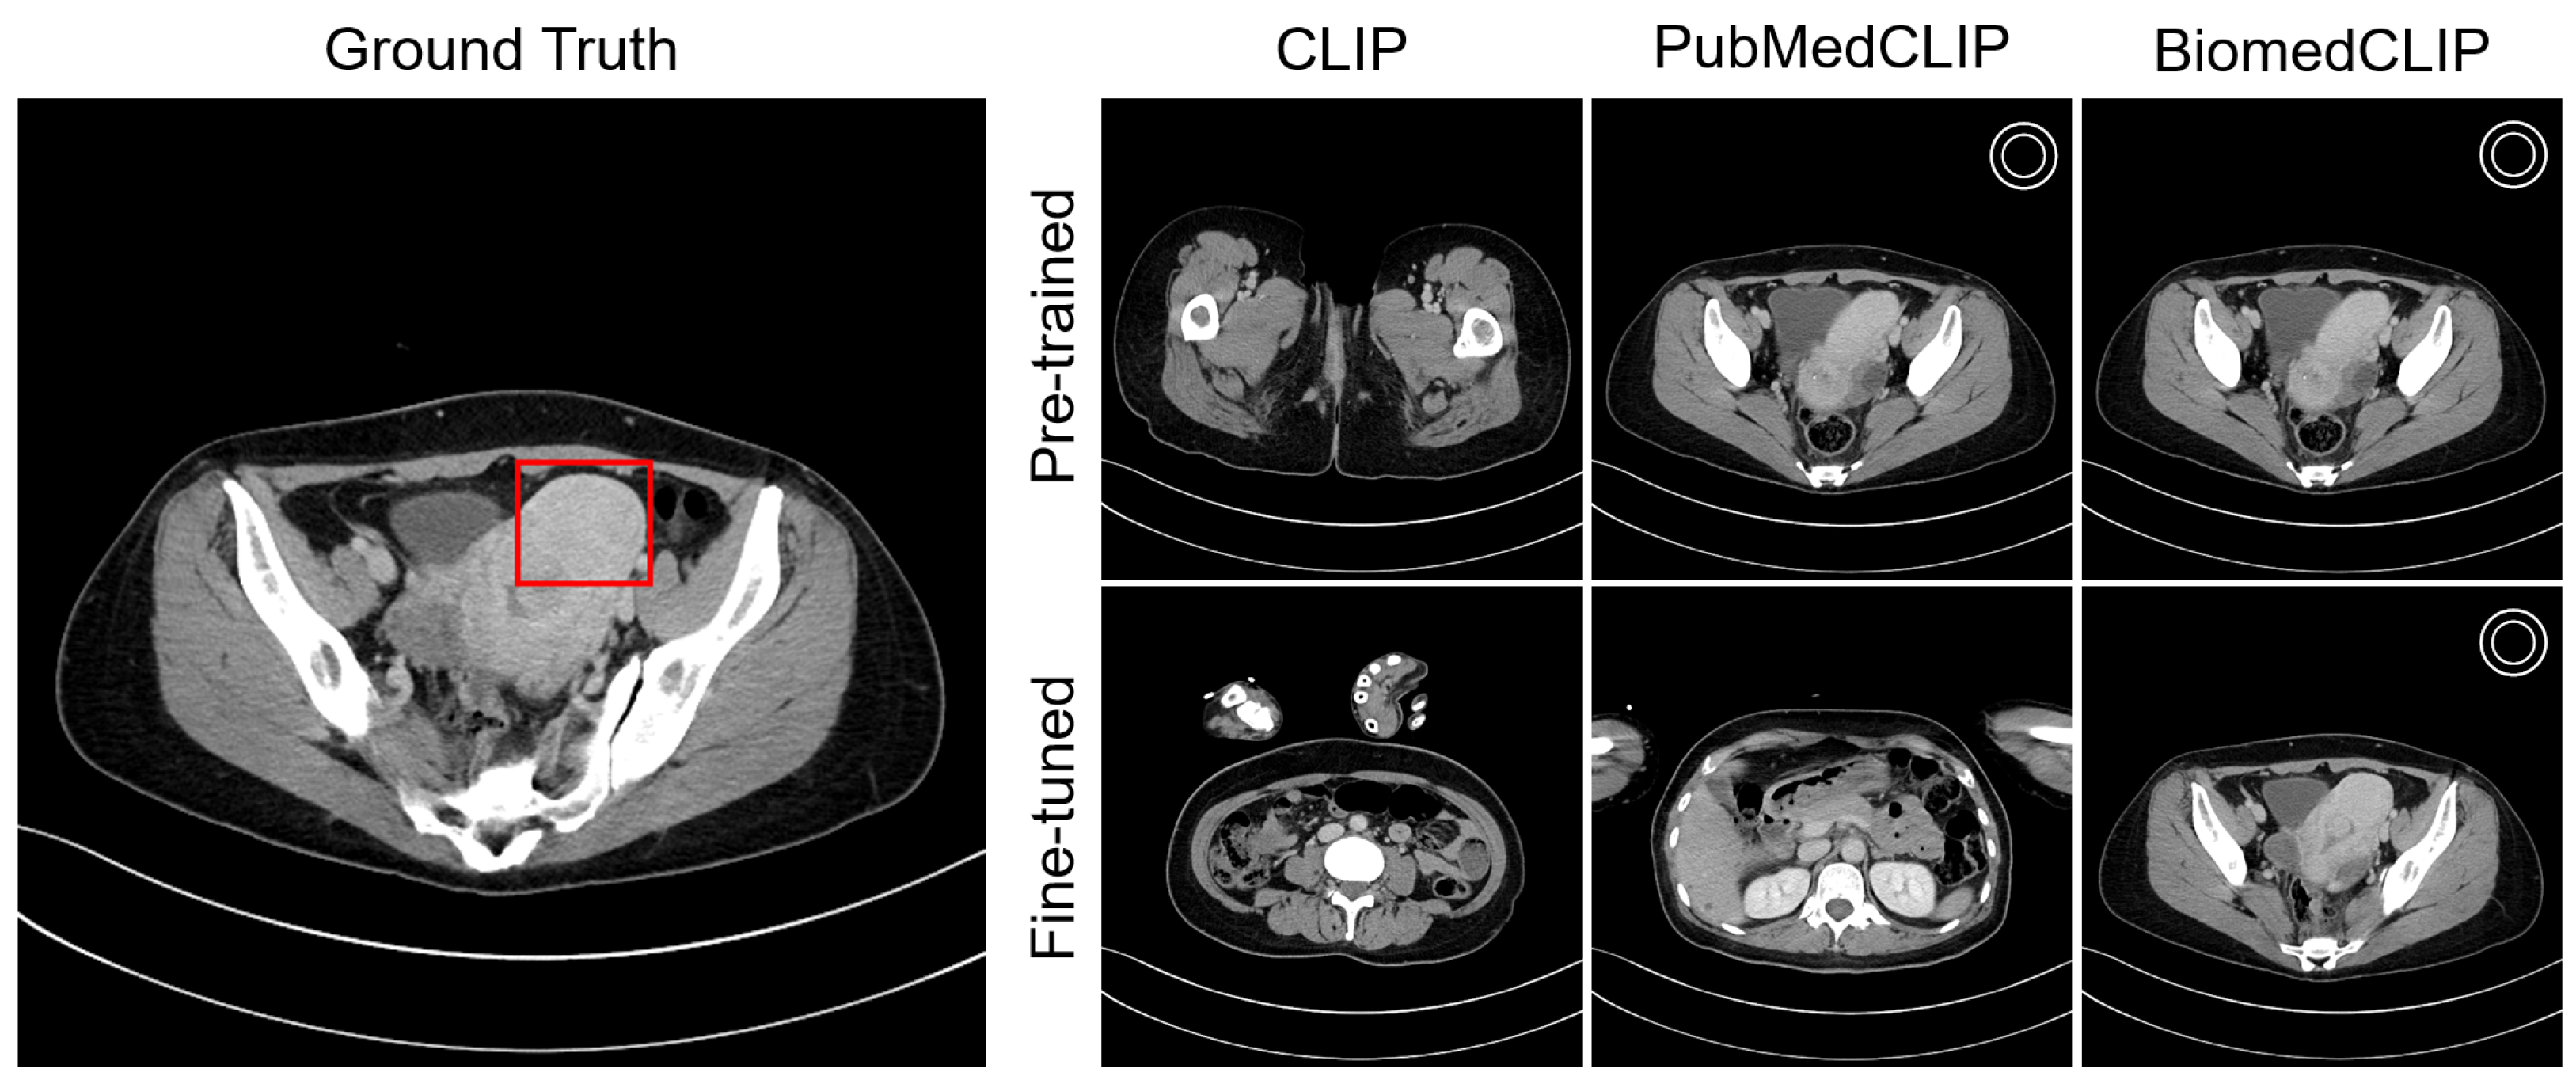

4.4. Visualization

Appendix C. Visualization

Appendix C.1. Lesion Awareness